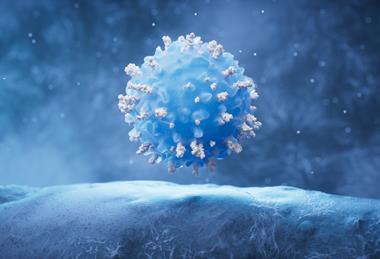

Anticipating adaptation: understanding and overcoming cancer drug resistance

Neil Bhowmick explores how understanding the mechanisms of cancer drug resistance has reframed our approach to treatment, revealing containment and control as realistic goals for therapeutic strategies.

KMA and LMA antigens emerge as high value targets for plasma cell dyscrasia treatment

Research published in Clinical Lymphoma, Myeloma and Leukemia identifies Kappa Myeloma Antigen and Lambda Myeloma Antigen as highly selective immunotherapy targets across plasma cell dyscrasias.